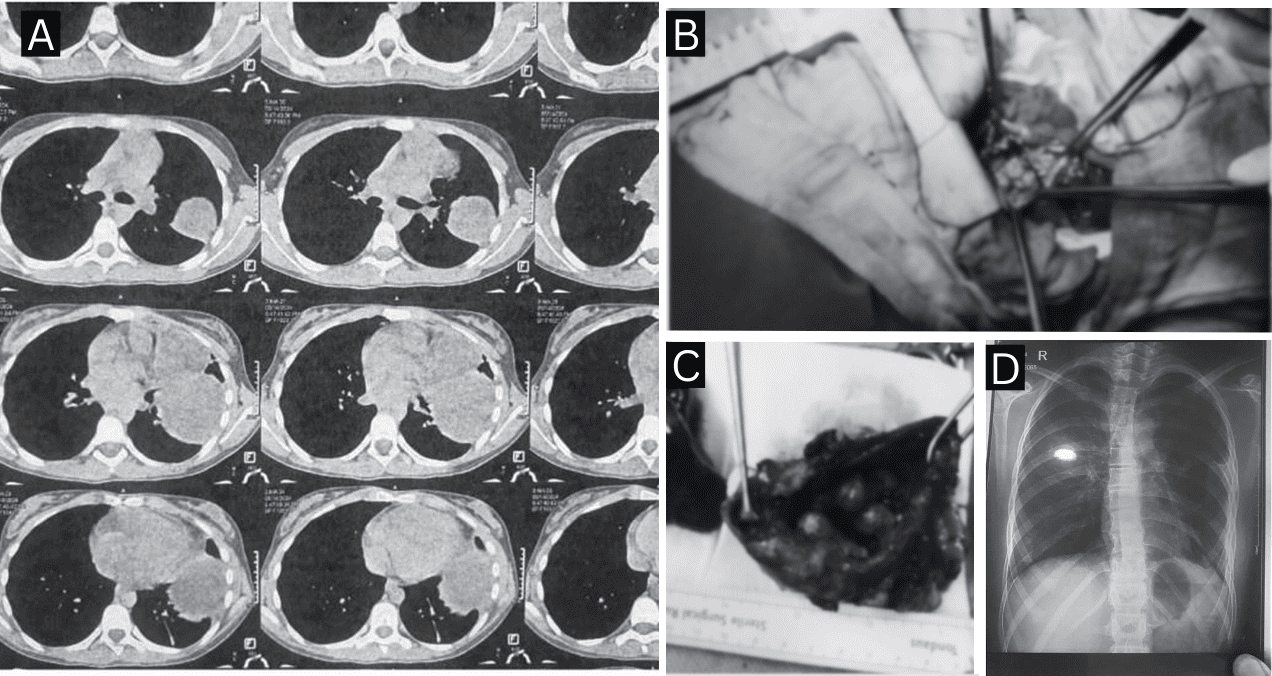

Dada la sospecha diagnóstica, se indicó resección quirúrgica. La paciente fue sometida a una toracotomía posterolateral izquierda, logrando la escisión completa de ambas lesiones.

La recuperación transcurrió sin complicaciones y la paciente fue dada de alta al séptimo día postoperatorio. La radiografía de control realizada al día 20 mostró resolución completa de las anomalías sin evidencia de recurrencia.

El estudio anatomopatológico confirmó el diagnóstico de un teratoma quístico maduro mediastínico, compuesto por tejido epitelial escamoso, glándulas sebáceas, folículos pilosos, epitelio gastrointestinal y músculo liso.

Asimismo, se identificó un quiste broncogénico infectado intrapulmonar, revestido por epitelio respiratorio ciliado, con evidencia de hemorragia alveolar y formación de abscesos.

La intervención permitió la resección completa de un teratoma mediastínico de 7.5 × 4.5 cm y de un quiste broncogénico de 11.5 × 5.5 cm. La resolución quirúrgica fue definitiva, sin complicaciones ni lesiones residuales, y con desaparición total de los síntomas respiratorios.